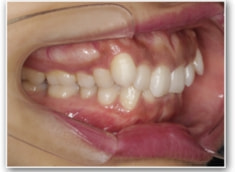

治療開始1年後